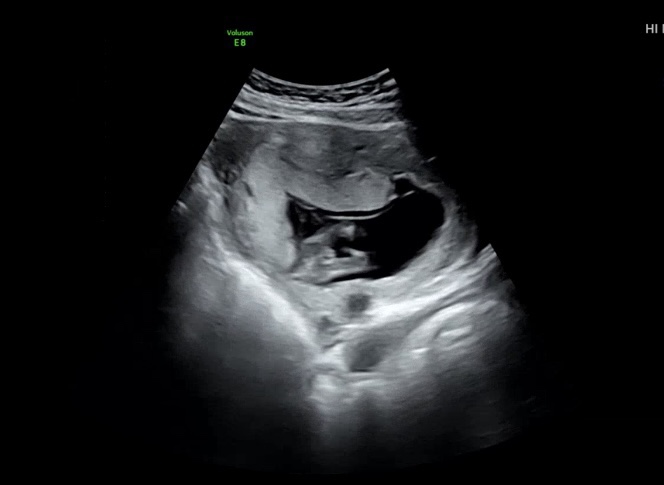

둘째임신) 13주, 15주 임신증상, 임산부 감기, 성별확인, 2차기형아검사

13주 5일차에 심한 감기에 걸려서 가래와 기침, 콧물이 동반했다. 기침할때마다 자궁도 너무 아프고 땡기고...